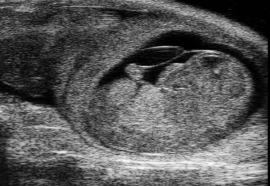

| sonographic unit | mouse day 13 |